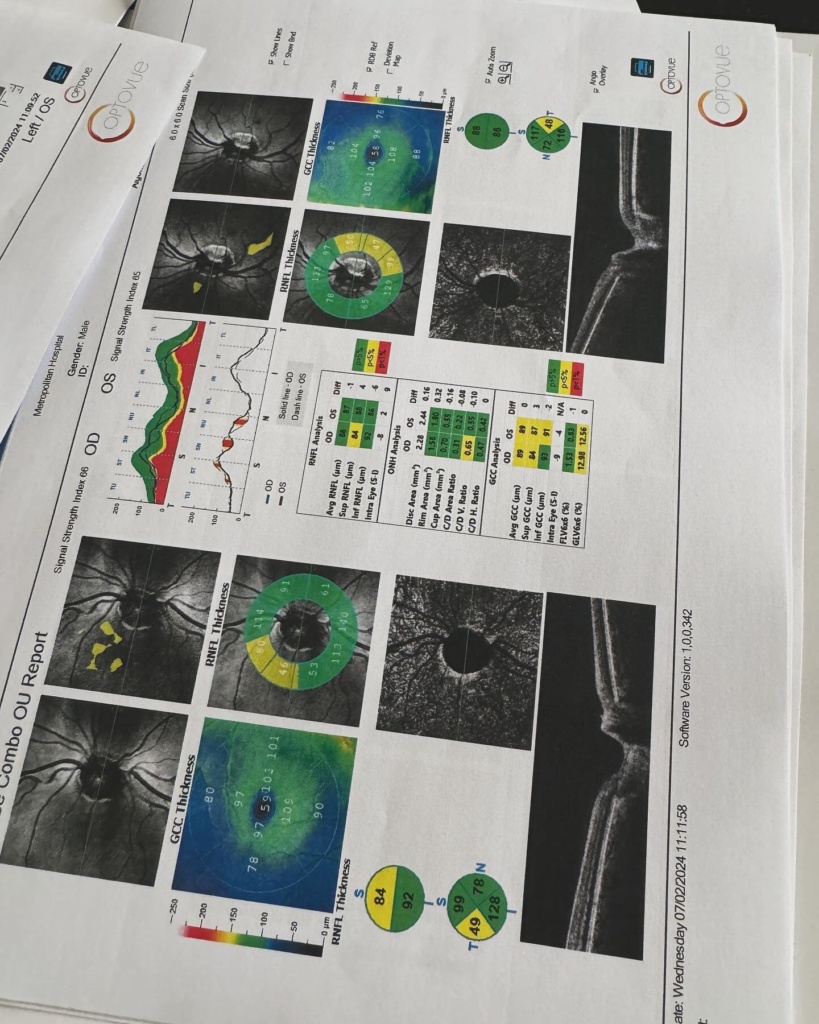

Ή μάλλον για τον τύπο που λέγεται Μάστορας. Ακούω κατά καιρούς διάφορες φήμες και έτυχε να ακούσω και τώρα κάποιες άλλες που δεν τιμούν οποίους τις διαδίδουν οπότε θα ανεβάσω μερικές φωτογραφίες από τις δύο δύσκολες τελευταίες εβδομάδες. Ο πιο σημαντικός λόγος που τις ανεβάζω είναι όμως για να μοιραστώ την ιστορία μου για την αμφοτερόπλευρη δακρυοαδενίτιδα.

Αιτία ο κοβιντ ο άτιμος… Ψάξτε το. Μπορεί και κάποιος από εσάς να υποφέρει από αυτήν αυτό τον καιρό και να μην ξέρει πώς να το διαχειριστεί.. Εγώ μπήκα στο νοσοκομείο και είχα την πιο απίστευτη γιατρό την Δήμητρα Π. να με προσέχει σε κάθε βήμα. Είμαι καλά τώρα όποτε πάμε γερά!», έγραψε χαρακτηριστικά ο Χρήστος Μάστορας.